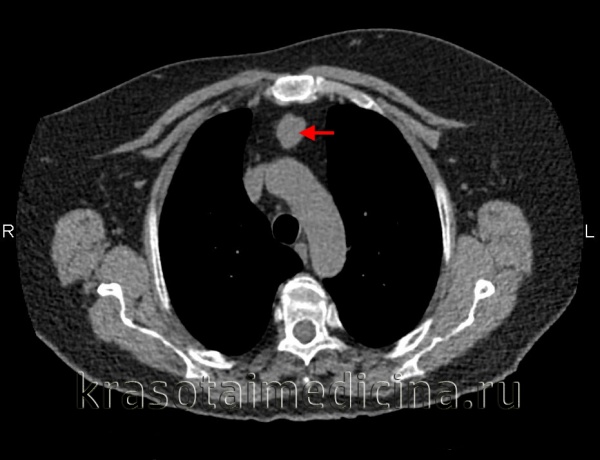

(Слева) КТ с контрастированием, аксиальный срез: определяется крупное поликистозное двустороннее образование шеи, почти полностью смещающее все нормальные ткани по окружности. У этого двухдневного новорожденного томограмма была получена для оценки распространения образования и планирования чрескожной склеротерапии.

3. КТ при лимфангиоме:

• Образование с четкими или нечеткими контурами

• Дольчатое с гиподенсными кистозными областями:

о Кистозные области не накапливают контраст

• Могут прорастать или смещать соседние органы

• Кальцификаты встречаются редко